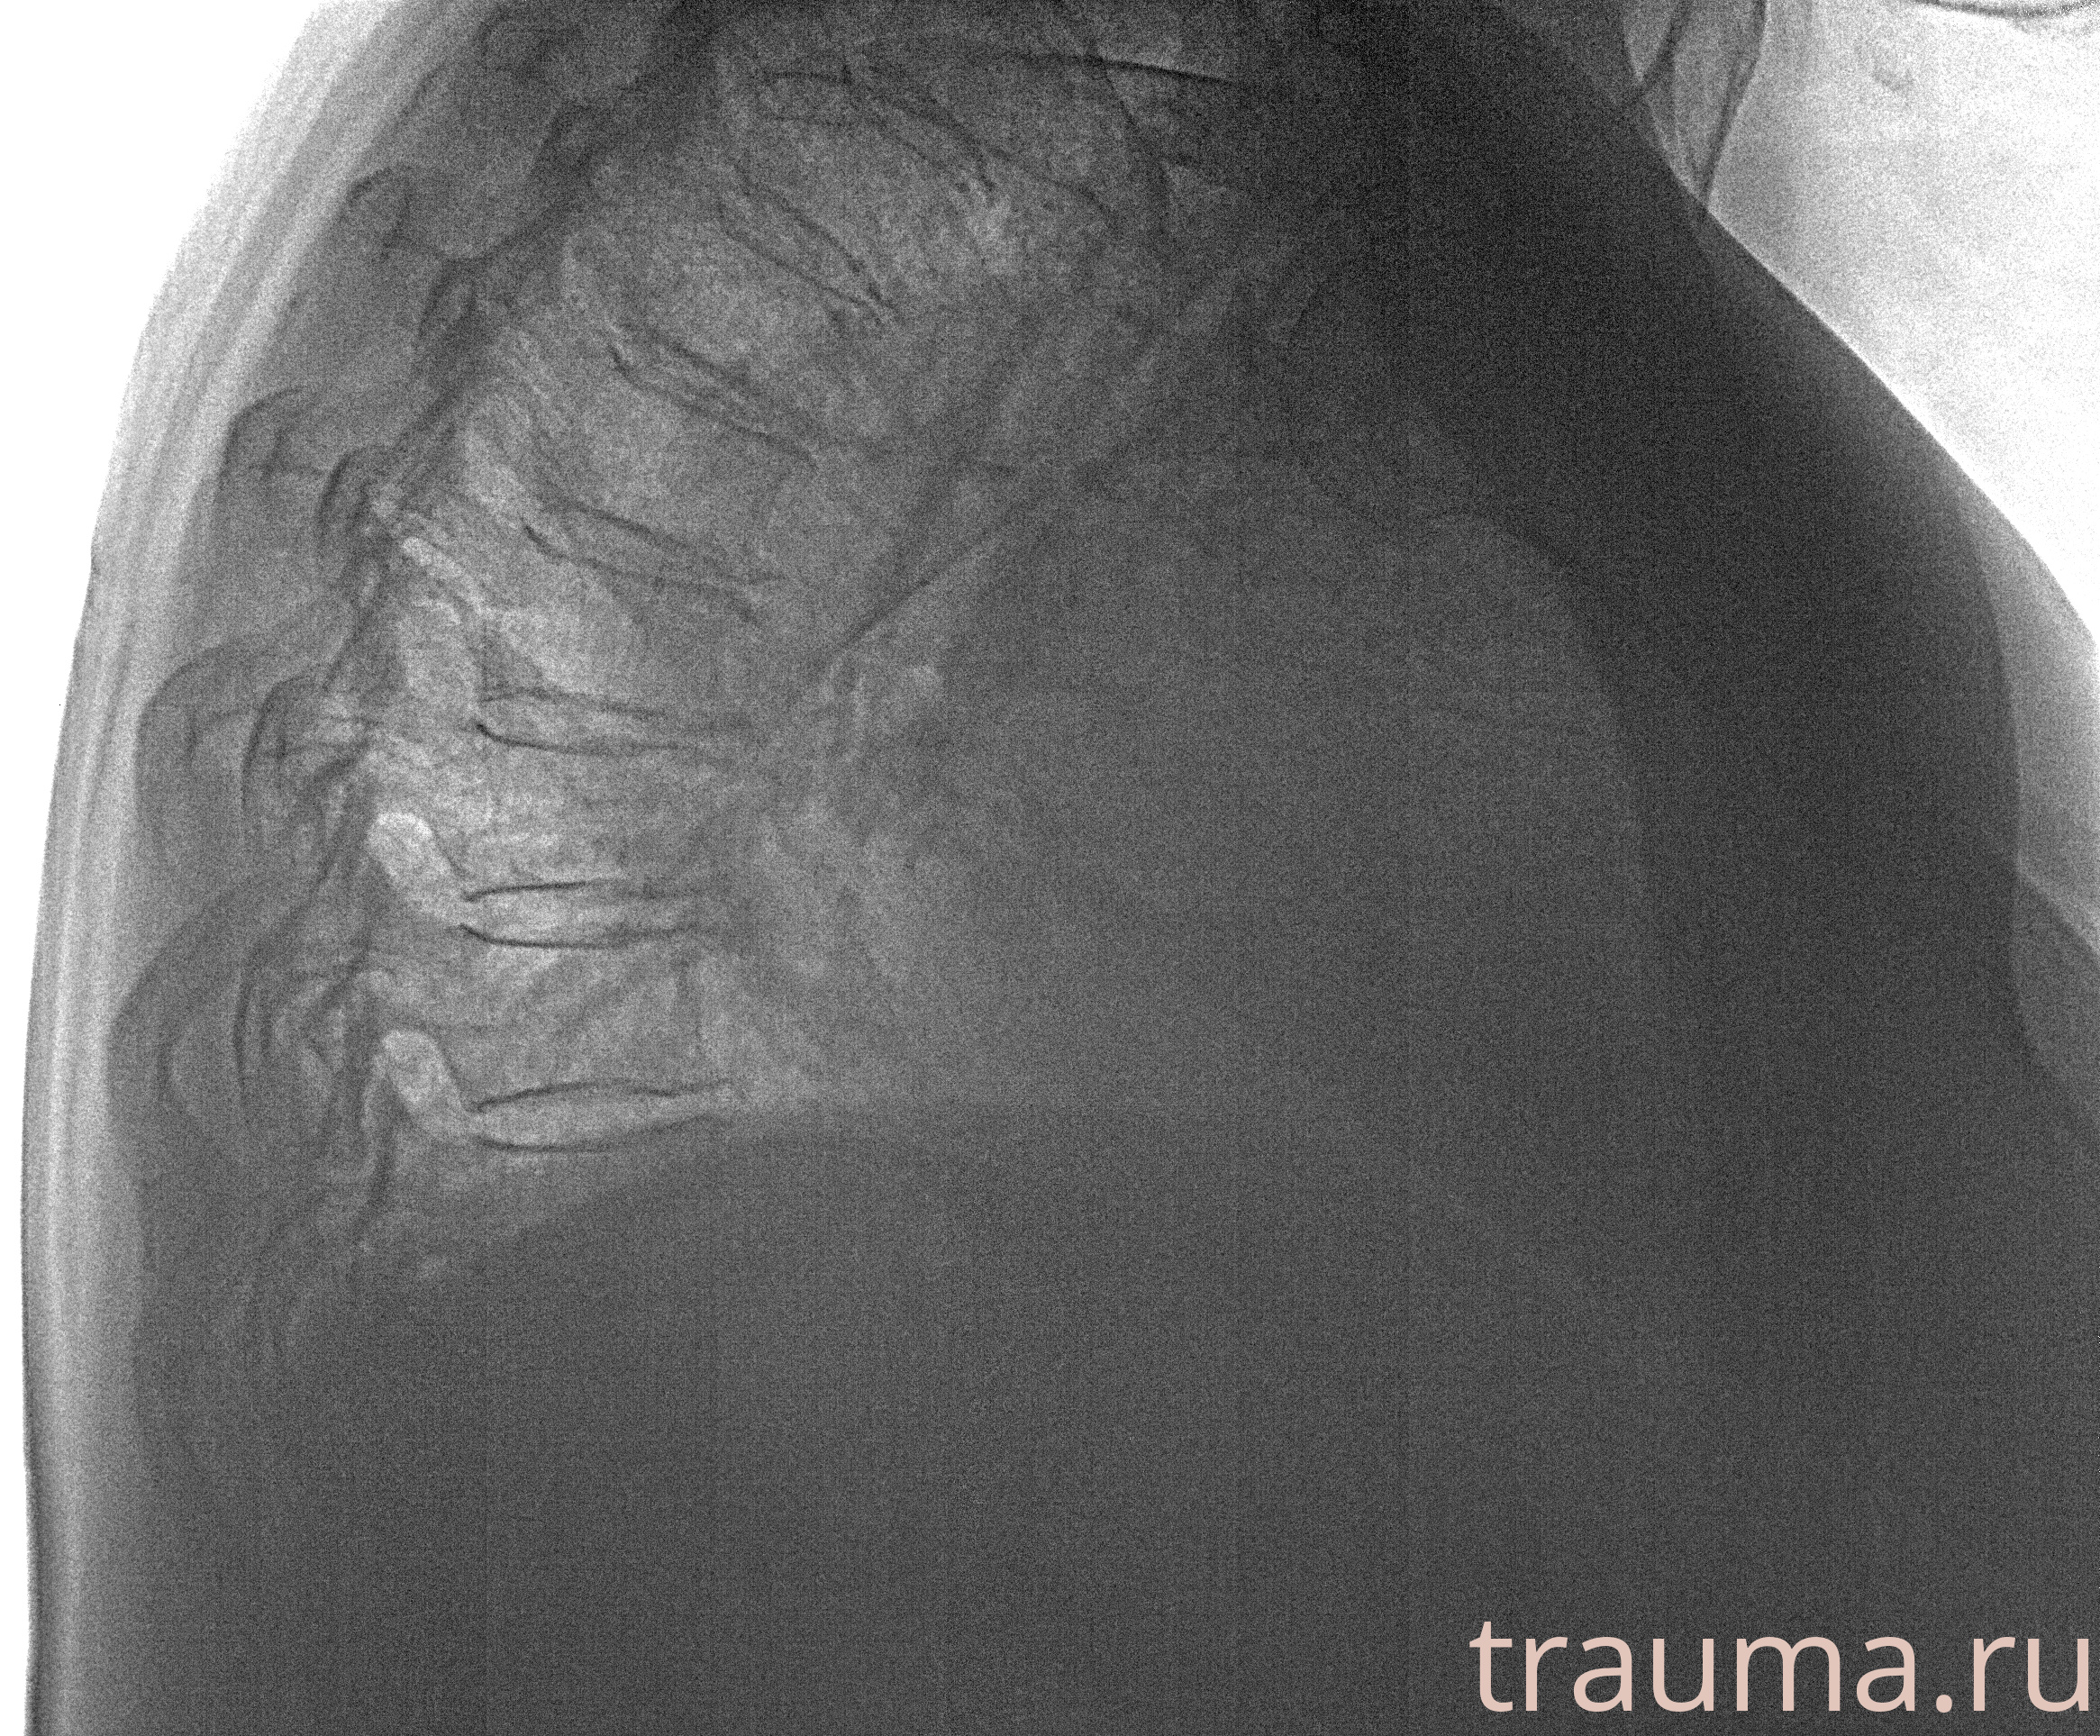

Рентген на дому: по вашему адресу приезжает врач-рентгенолог, травматолог-ортопед с мобильным рентгеновским аппаратом, проводит диагностику травмы или заболевания, делает необходимые рентгенограммы, дает рекомендации по дальнейшему лечению. Получить качественные снимки в домашних условиях возможно благодаря уникальной методике, разработанной МосРентген Центром для института  Склифосовского